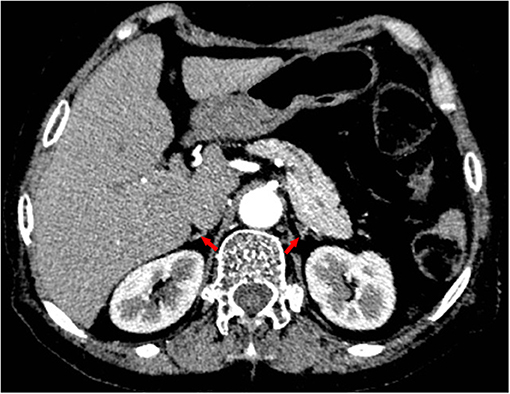

Given her long-term dexamethasone treatment and dramatic manifestations consistent with adrenal insufficiency, we tested her basal plasma cortisol and simultaneous corticotropin (ACTH) levels. It turned out that her basal plasma cortisol level was extremely low (0.65 μg/dL; normal 8 a.m. cortisol level: 10.4–26.4 μg/dL) and that ACTH level was low (4.32 pg/mL; normal 8 a.m. ACTH level: 6–40 pg/mL). Continuous cortisol monitoring revealed that her plasma cortisol was constantly deficient (Figure 3). Additionally, her abdominal enhanced computed tomography revealed atrophic bilateral adrenal glands (Figure 4), indicating long-standing and severe adrenal insufficiency. Further autoantibody assays were negative. In addition, her brain magnetic resonance imaging (MRI) and other pituitary hormones (growth hormone, luteinizing hormone, follicle-stimulating hormone, and prolactin) levels were normal. Therefore, the final diagnosis was dilated cardiomyopathy with tertiary adrenal insufficiency.

FIGURE 4

www.frontiersin.org

Figure 4. Contrast-enhanced computed tomography revealing atrophic bilateral adrenal glands (red arrows).

DCM is an etiologically heterogeneous disorder. Early diagnosis and prompt treatment of the underlying disease are of great significance (13). For our patient, her long-term use of dexamethasone and adrenal atrophy on computed tomography revealed that she suffered from chronic and severe adrenal insufficiency. More importantly, her first episode of heart failure and shock occurred 3 years after intermittent use of dexamethasone, and these episodes were quite peculiar because even transient anger could cause acute-onset of dyspnea and shock. In addition, standard heart failure and antishock treatment failed, but hydrocortisone replacement therapy dramatically improved her symptoms and echocardiographic parameters. Although we could not exclude the coincidence of idiopathic dilated cardiomyopathy with tertiary adrenal insufficiency with 100% certainty, in the absence of other risk factors for DCM, it is quite reasonable to conclude that our patient's refractory cardiomyopathy resulted from tertiary adrenal insufficiency. For our patient, the cardiac dysfunction caused by tertiary adrenal insufficiency along with superimposed stress precipitated her dramatic and recurrent episodes of heart failure and shock. However, her non-specific symptoms often obscured the underlying etiology, resulting in ongoing adverse left ventricular remodeling. As a result, the damage to her heart was so severe that hydrocortisone and heart failure treatments failed to reverse this process, and she was at growing risk for malignant ventricular dysrhythmia. In this case, CRT-D might be life-saving and improve her prognosis.